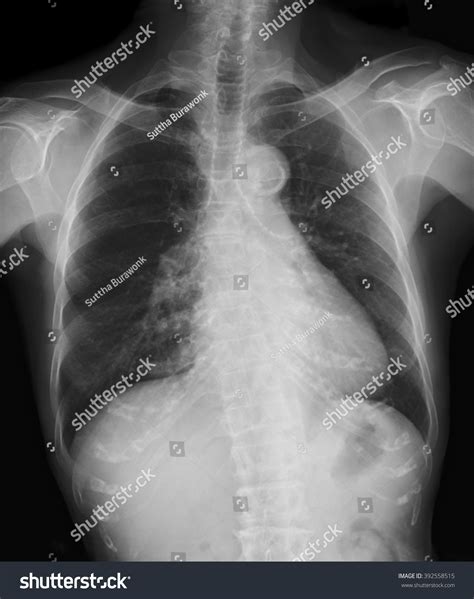

A bronchitis X ray is a crucial diagnostic tool that helps healthcare providers visualize the lungs and bronchial tubes. This imaging technique uses X-rays to create detailed images of the chest, allowing doctors to identify any abnormalities or inflammation. The bronchitis X ray can reveal:

• Inflammation and swelling of the bronchial tubes

• Presence of mucus or fluid in the lungs

• Signs of infection or pneumonia

• Structural abnormalities in the lungs

Interpreting the results of a bronchitis X ray requires the expertise of a radiologist or healthcare provider. The images are carefully examined for signs of inflammation, infection, or other abnormalities. Key findings that may be noted include:

• Increased density or opacity in the lungs, indicating inflammation or fluid buildup

• Thickening of the bronchial walls

• Presence of nodules or masses

• Signs of pneumonia or other respiratory infections